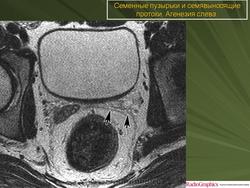

Radiology Key

Мужская репродуктивная система: простата, семенные пузырьки и мошонка

https://radiologykey.com/male-reproductive-system-prostate-gland-seminal-vesicles-and-scrotum/